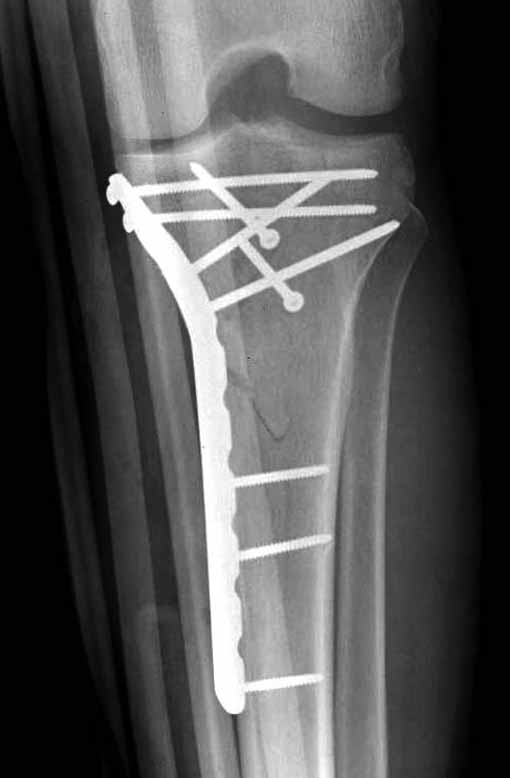

Двухколоннный перелом тибиал плато с вовлечением проксимального диафиза. Внутрисуставной компонент без смещения, и такой перелом можно лечить любым из описанных методов, о которых говорят наши коллеги.

Удобно аппаратом Илизарова или интрамедуллярным гвоздем. Гвозди не так сложно, как пугают, тем более Александр готов помощь с методичкой. Сперва надо установить компрессирующие шурупы на мыщелки. Давно отказались в пользу 3.5-4.0 мм кортикальных вместо толстых спонгиозных, потому что не доказаны преимущества толстых шурупов. Тонкие шурупы в субхондральной зоне смотрятся намного элегантнее, чем толстые 6.5.

Это мероприятие превращает перелом в простой диафизарный, который легко можно фиксировать гвоздем. Шурупы надо установить сзади предполагаемого места введения гвоздя.

Частая ошибка, когда фиксацию двух колонного перелома проводят одиночной пластиной, т.е с одной стороны, и такая фиксация не удерживает, происходит вторичноое смещение. Необходимо нейтрализовать второй пластиной или дополнительным наружным фиксатором.

Если у вас, кроме пластины, нет другого альтернативного варианта, тогда, учитывая мягкотканые проблемы с наружной стороны, я бы рекомендовал операцию делать в два этапа. Преимущества, сперва репозиция и фиксация перелома с медиальной стороны, а затем, после улучшения состояния мягких тканей, зафиксировать с латеральной стороны. Современные пластины имеют латеральный Jig для перкутанных мини доступов.

В приложении этапы фиксации Both Column Fx и пластиной Synthes для плеча при переломе медиального мыщелка.